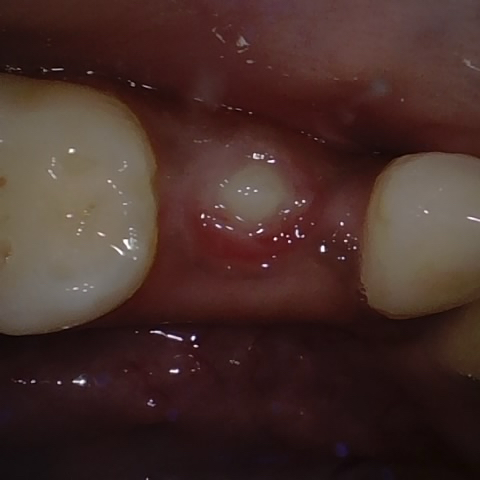

Annotated as "Good"